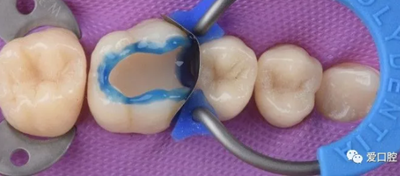

⑶牙本質(zhì)粘接推薦使用自酸蝕粘接系統(tǒng)。

②自酸蝕粘接劑對牙髓幾乎沒有刺激,可以直接用于未露髓的牙本質(zhì)層。使用氫氧化鈣間接蓋髓在多數(shù)情況下是不必要的,如若使用,也應(yīng)盡可能減少這些制劑的覆蓋面積。

③分層充填有助于減少聚合應(yīng)力,降低邊緣微滲漏所致的牙髓刺激。